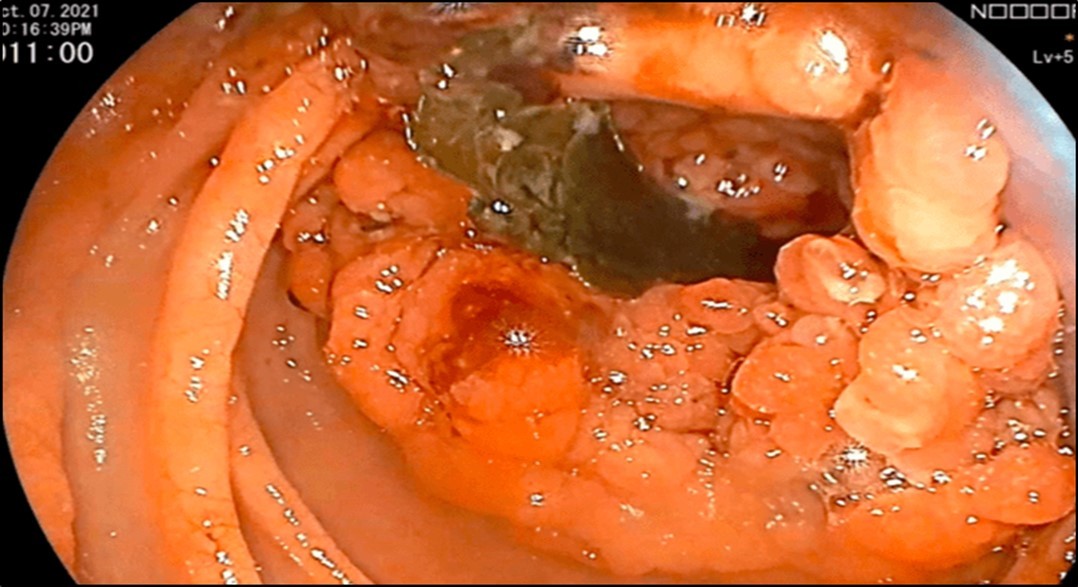

There was no evidence of malignancy or IBD seen during both endoscopic procedures. Computed tomography (CT) scan of the whole abdomen was done which showed inflammatory changes involving the cecum and adjacent duodenum and ileum with coloenteric fistulae. There was noted progression of abdominal lymphadenopathies as well as ascites. Main consideration was an infectious disease process (i.e. TB) (Figure 2, Figure 3, Figure 4 to Figure 5).

Figure 2.Colonoscopy finding of a circumferential, obstructive and nodular mass with areas of necrosis with a pathologic lumen believed to be communicating with the lumen seen on the previous EGD was seen at the proximal transverse which precluded further advancement of the scope